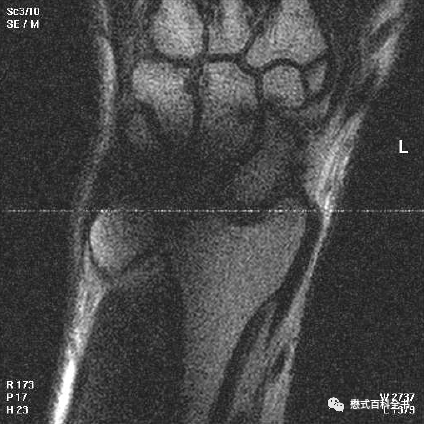

图3~5:Ghosting伪影的表现

一般Ghosting伪影产生的原因主要是硬件系统不稳定导致的。比如:射频系统不稳定、梯度系统不稳定、磁场均匀度等。

Ghosting伪影的图像表现是在相位编码方向出现多个连续的重影(幽灵样影像),这种连续的多个重影还是比较好识别的。